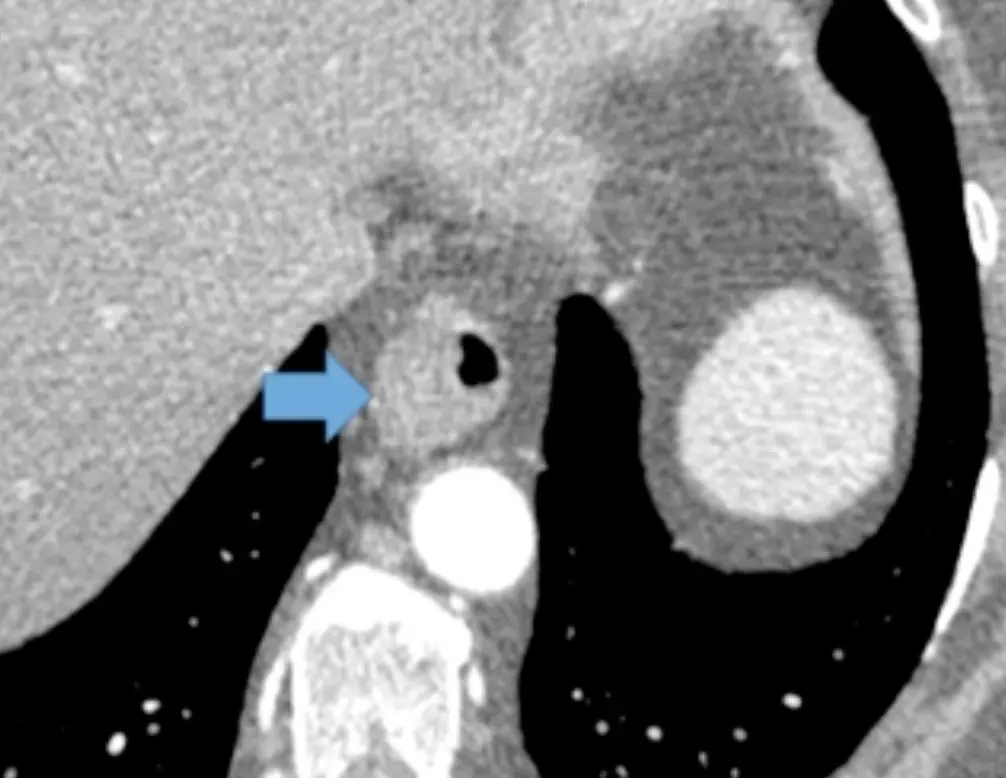

Example: 75 y/o with asymmetric thickening of esophagus prompting endoscopy â Dx: Carcinoma.